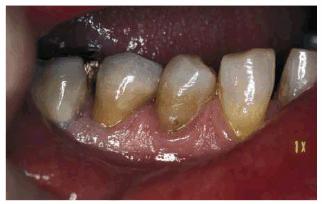

Figur 323s1823d e 18-8A: This 6-year-old girl fractured her maxillary central incisors in an accident.

Figur 323s1823d e 18-8B and C: The two central incisors were beveled and bonded with composite resin.

Figur 323s1823d e 18-8D and E: Ten years later, the patient still retains her original bonding, although reveneering has been done to maintain appearance